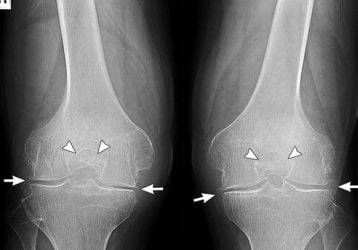

Эндопротезирование коленного сустава: подробное руководство к операции

Первичное и ревизионное эндопротезирование коленного сустава. Показания и противопоказания к операции, подготовка. Срок службы. ЛФК при реабилитации. Получение квоты.

Артроскопия коленного сустава: что это такое, техника выполнения операции

Что такое артроскопия коленного сустава, для чего выполняют данный вид операции. Показания и противопоказания к артроскопии. Подготовка пациента и техника проведения операции.

Замена коленного сустава: подготовка и ход операции

Замена коленного сустава: показания к операции и противопоказания к эндопротезированию. Виды протезов, подготовительные и операционные этапы.